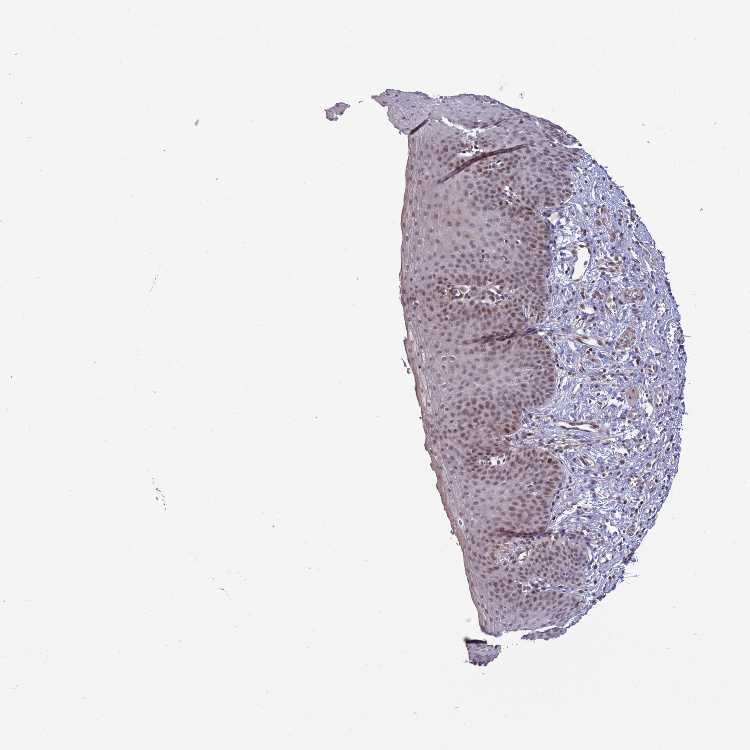

ESOPHAGUS - Antibody stainingi

Antibody staining in the annotated cell types in the current human tissue is reported as not detected, low, medium, or high, based on conventional immunohistochemistry profiling in selected tissues. This score is based on the combination of the staining intensity and fraction of stained cells.

Each image is clickable and will lead to virtual microscopy that enables deeper exploration of all samples and also displays staining intensity scores, fraction scores and subcellular localization as well as patient and tissue information for each sample.

Antibody HPA045761

Squamous epithelial cells Medium